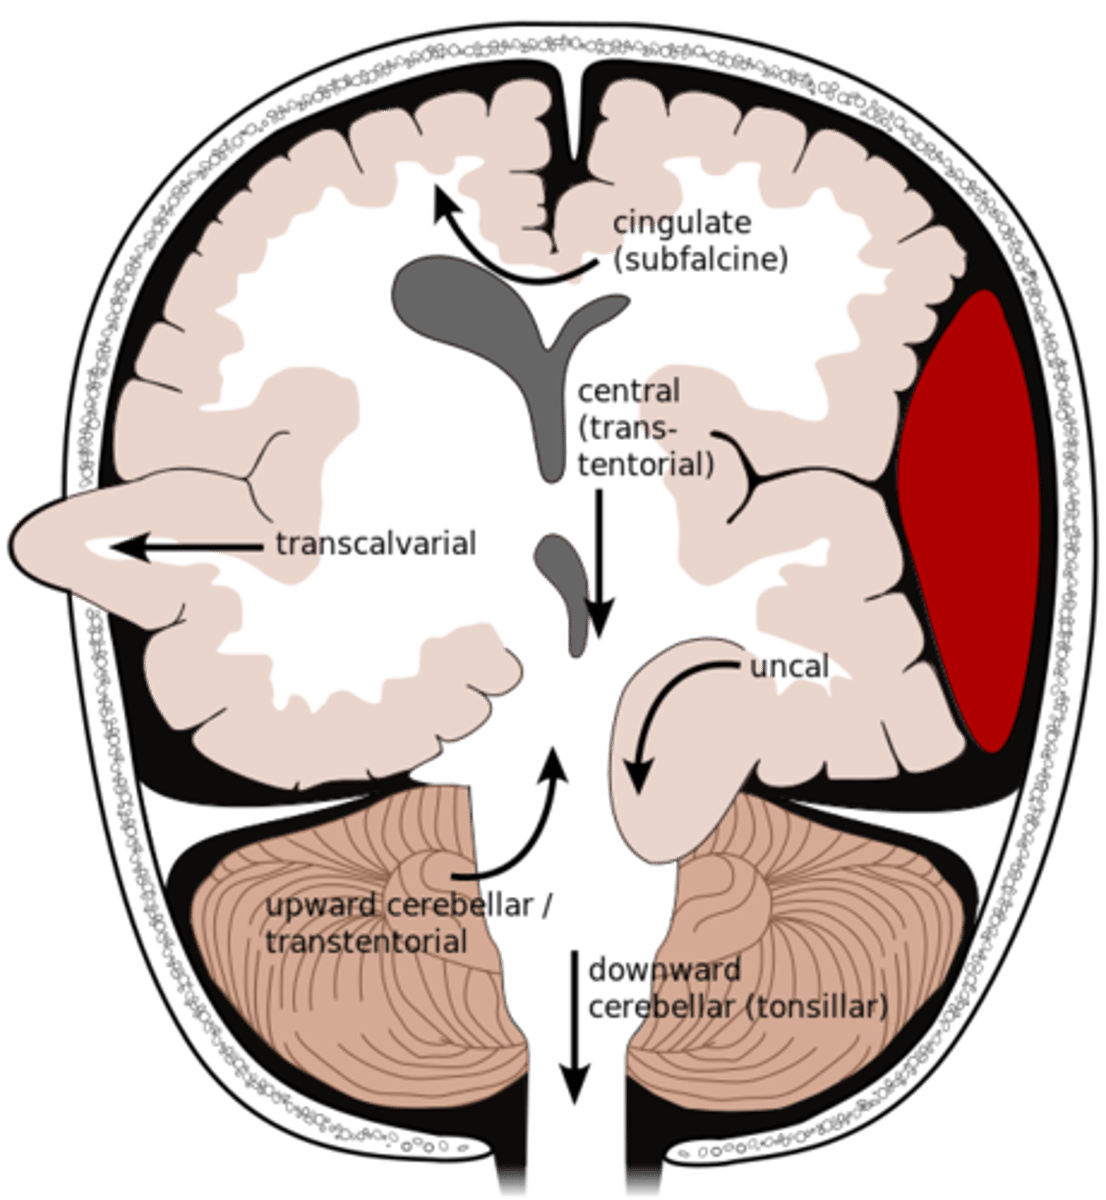

What is an uncal herniation?

most common.

unilateral lesions forces uncus of temporal lobe to displace and compress on the midbrain.

What is a central herniation?

Downward shift of cerebral hemisphere, compressing the brainstem

What is a cingulate herniation?

shift of brain tissue from one hemisphere to the other. Compress anterior cerebral artery.

Ischemic stroke may occur

What is a transcalvarian herniation?

brain begins to herniate outside of the skull. the brain will squeeze out of fractures, burr holes, or surgical incisions.

What is an upward herniation?

displacement of the cerebellum upward

What is a cerebellar Tonsillar herniation?

displacement of cerebellar tonsils downward this compressing the pons/medulla

s/s: alterations in resp. and cardiac functions- rapidly progressing to cardiac arrest, Headache and neck stiffness, reduced muscle tone